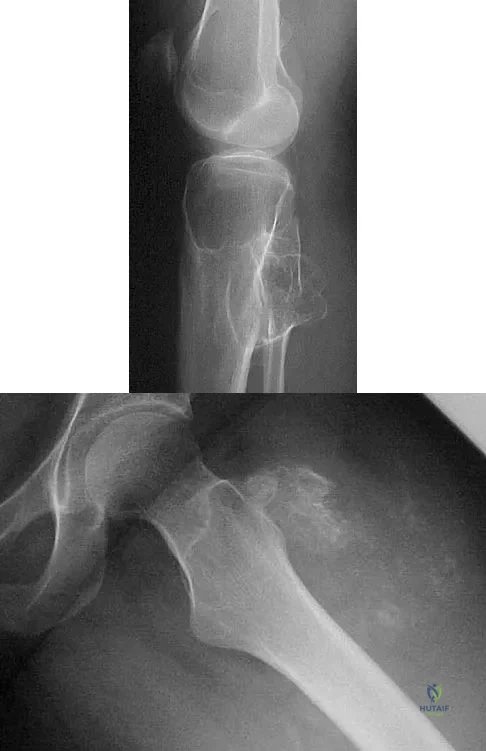

Question 51

Figure 22 shows the radiographs of a 16-year-old boy who injured his elbow in a fall 1 year ago. Although he has no pain, he reports restricted forearm rotation and elbow flexion. What is the most likely diagnosis?

A 13-year-old boy hyperextends his knee while playing basketball and reports a pop that is followed by a rapid effusion. A lateral radiograph is shown in Figure 4. Initial management consists of attempted reduction with extension, with no change in position of the fragment. What is the next most appropriate step in management?

Explanation